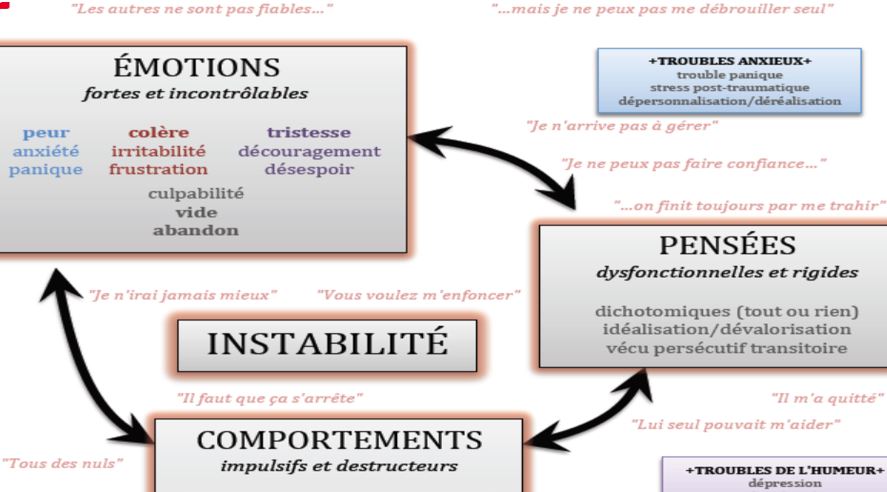

♠ 9

Instabilité dans sa vie  Chaos cérébral  Lien entre les pensées, émotions ,comportements et l’instabilité  Cliquez pour agrandir |

► Comme tout le monde ils ont des objectifs de vie à chaque

âge de leur vie (but professionnel, recherche de l’âme

sœur idéale), mais cette confusion cérébrale rend leur atteinte

difficile. – C‘est surtout une quête quotidienne de motivation (pour la concentration), d’états énergétiques suffisants (pour accomplir les tâches ou être en relation), et de reconnaissance vis à vis des autres (pour l’estime de soi), qui les fait donc avancer, ce qui peut s’avérer non cohérent pour leurs objectifs à long terme. ► Certains ont l’impression de n’avoir pas de métiers dans la durée, d’autres ne se sentent nulle part chez eux et déménagent très souvent, ou partent impulsivement à l’autre bout de la planète sauver le monde ou se confronter à une vie non routinière, avec des dangers qui vont les canaliser pour un temps. – Beaucoup font un point sur leur vie toutes les 5 mn en constatant un manque d’accomplissement qui est justement dû en partie au fait qu’ils y réfléchissent trop. – Les plus surdoués cherchent un sens à leur vie dès le plus jeune âge. ► On observe souvent une instabilité non maitrisée dans leur vie personnelle et/ou professionnelle. – Cela peut leur convenir sur le court terme, mais c’est souvent une source de manque financier, affectif et familial sur le long terme. – Une désocialisation ou une superficialité dans les relations peuvent alors devenir le principal problème bien au-delà du déficit d’attention, bien que certains assument leurs choix. ⇒ Une crise du milieu de vie ou un burnout peut leur faire prendre conscience qu’il faut qu’ils changent en profondeur et la découverte du TDAH est un atout pour mieux se connaitre et trouver des solutions. ► Un foisonnement d’idées et de projets les amènent souvent à un chaos des pensées et des émotions . – Ils ne vivent pas l’instant présent, mais fabulent intérieurement sur ce qui se passe, se font des commentaires dans leur tête sans arrêt et pensent à tout autre chose que l’action ou la conversation en cours. – Donc ils sont plus facilement assaillis par des pensées et des émotions négatives à force d’échecs répétés, et cela peut les déstabiliser. – Avec ce chaos cérébral et ces émotions paralysantes ou au contraire trop captivantes, beaucoup ont du mal à s’exprimer clairement même sur un sujet qu’ils connaissent bien. – Beaucoup ne peuvent pas lire un livre, ou tout au plus les premières pages si c’est le sujet du moment qui les passionne ► C’est plus que de la distraction ou une simple difficulté à organiser ses idées, tout se bouscule dans leur tête avec une pensée en arborescence, y compris lorsqu’il faut choisir des objectifs, prendre des décisions lors de moments importants. – Ils pensent à plusieurs choses en même temps et souvent au mauvais moment. – Par exemple, pendant un examen, une étudiante déclare avoir alterné entre le sujet de l’épreuve, la dispute avec sa mère de la veille, la liste de ses courses du jour et le sport qu’elle pratiquera l’année suivante, mais aussi des centaines de pensées furtives et incohérentes générées par l’émotion de l’examen. – Heureusement dans son cas, la concentration est revenue pendant la dernière heure où elle n’a plus eu le choix grâce à un stress positif survenu de lui-même. ► La plupart notent aussi l’arrêt de ce chaos et une plus grande lucidité lorsqu’ils n’ont plus le choix, ou dans l’urgence, ou encore quand ils sont proches d’un danger physique pour eux-mêmes ou les autres. – Certains orientent donc leur vie vers des activités autour de l’urgence, du danger ou du sauvetage des autres ce qui amène aussi du sens à leur vie. – Très peu arrivent à s’assoir tranquillement seul sur un banc public. |